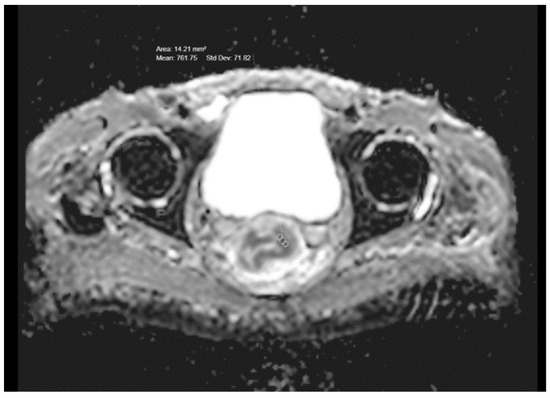

A statistically significant correlation was found when the ADC values in the rectal tumors of different T stages were compared (p = 0.039)—those with higher T stages showed lower ADC values (Figure 1b and Figure 2; Table 1). The mean ADC values in T1-stage tumors (5 patients) and T2-stage tumors (14 patients) were highest at 887 and 881, and the mean ADC value in T3 (38 patients) was 819 and in T4 (18 patients) was 776. No significant correlation was found between the ADC values of T3- and T4-stage tumors (p = 0.36) but T3- and T4-stage tumors showed significantly lower ADC values when compared to T1- and T2-stage (p < 0.05).

Figure 2. Pretreatment ADC value in a T3-stage rectal cancer.

Medicina 59 02162 g002